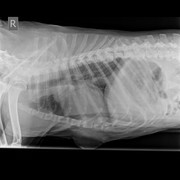

11 августа мы отвезли Федю в ДВ. Опухоль не одна, а по всему телу. Отобрали анализы, сделали рентген, чтобы сразу проверить на метастазы. Отобрали анализ мочи, тк Федя очень много пьет. Анализы крови неплохие, в моче есть бактерии и кокки (назначили Ципрофлоксацин на неделю).

12 августа были у Исаченко. Он отобрал цитологию из большой опухоли и одной поменьше на груди. На груди оказалась не опухоль, просто жировая ткань. Большая опухоль оказалась неоднородной, то есть можно провести цитологию жидкости (она оказалась без патологий), а вот мягкую ткань можно продиагностировать только через гистологию. То есть после операции, если мы решим её делать. На данный момент срочности нет, она не болит и не беспокоит его. Есть опасения наркоза, тк пес возрастной. На данный момент лечим инфекцию в мочевом, на этой неделе повтор анализа мочи и УЗИ.